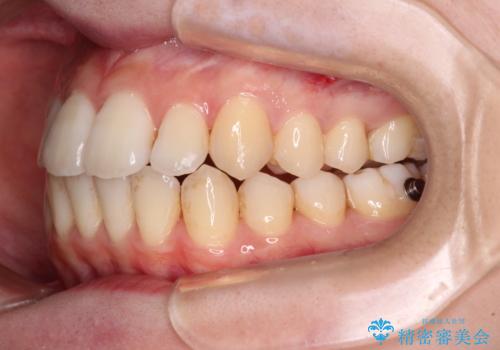

【モニター】前歯の前突感とクロスバイトをインビザラインで改善

- 前歯の突出感とクロスバイトが気になり、インビザラインによる矯正治療を希望して来院された患者様です。

上顎側切歯(上の真ん中から2番目の歯)が舌側転位している場合、インビザラインでは仕上げきれないことが多く、更には無理して動かそうとすると歯髄壊死を起こすリスクが高いと言われています。

インビザラインで歯列を移動する前に、上顎前歯をワイヤー矯正で整え、その後上下歯列をインビザラインにて矯正治療を行うこととしました。

舌側転位している側切歯特有の、切縁の位置が不揃いであったり、根元が内側に引っ込んだ状態であったりという、インビザライン独特の仕上がりになることなく、きれいに整った歯列とすることができました。